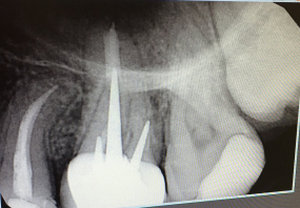

Здравствуйте. При принятии твердой и сладкой пищи, а также при ежедневной чистке зубов возникает ноющая боль в зубе (крайний левый на нижней челюсти). Стоматолог сказал, что есть небольшой кариес, поставили пломбу. Прошло уже три дня, а зуб всё равно ноет при накусывании. От чего это может быть и что делать в данной ситуации?

Добрый день . Скорее всего ваш стоматолог поставил неправильный диагноз или пломба завышает . Рекомендую обратиться на очный прием и после снимка вам все подробно расскажут. Не тяните , потеря времени может привести к потере зуба.